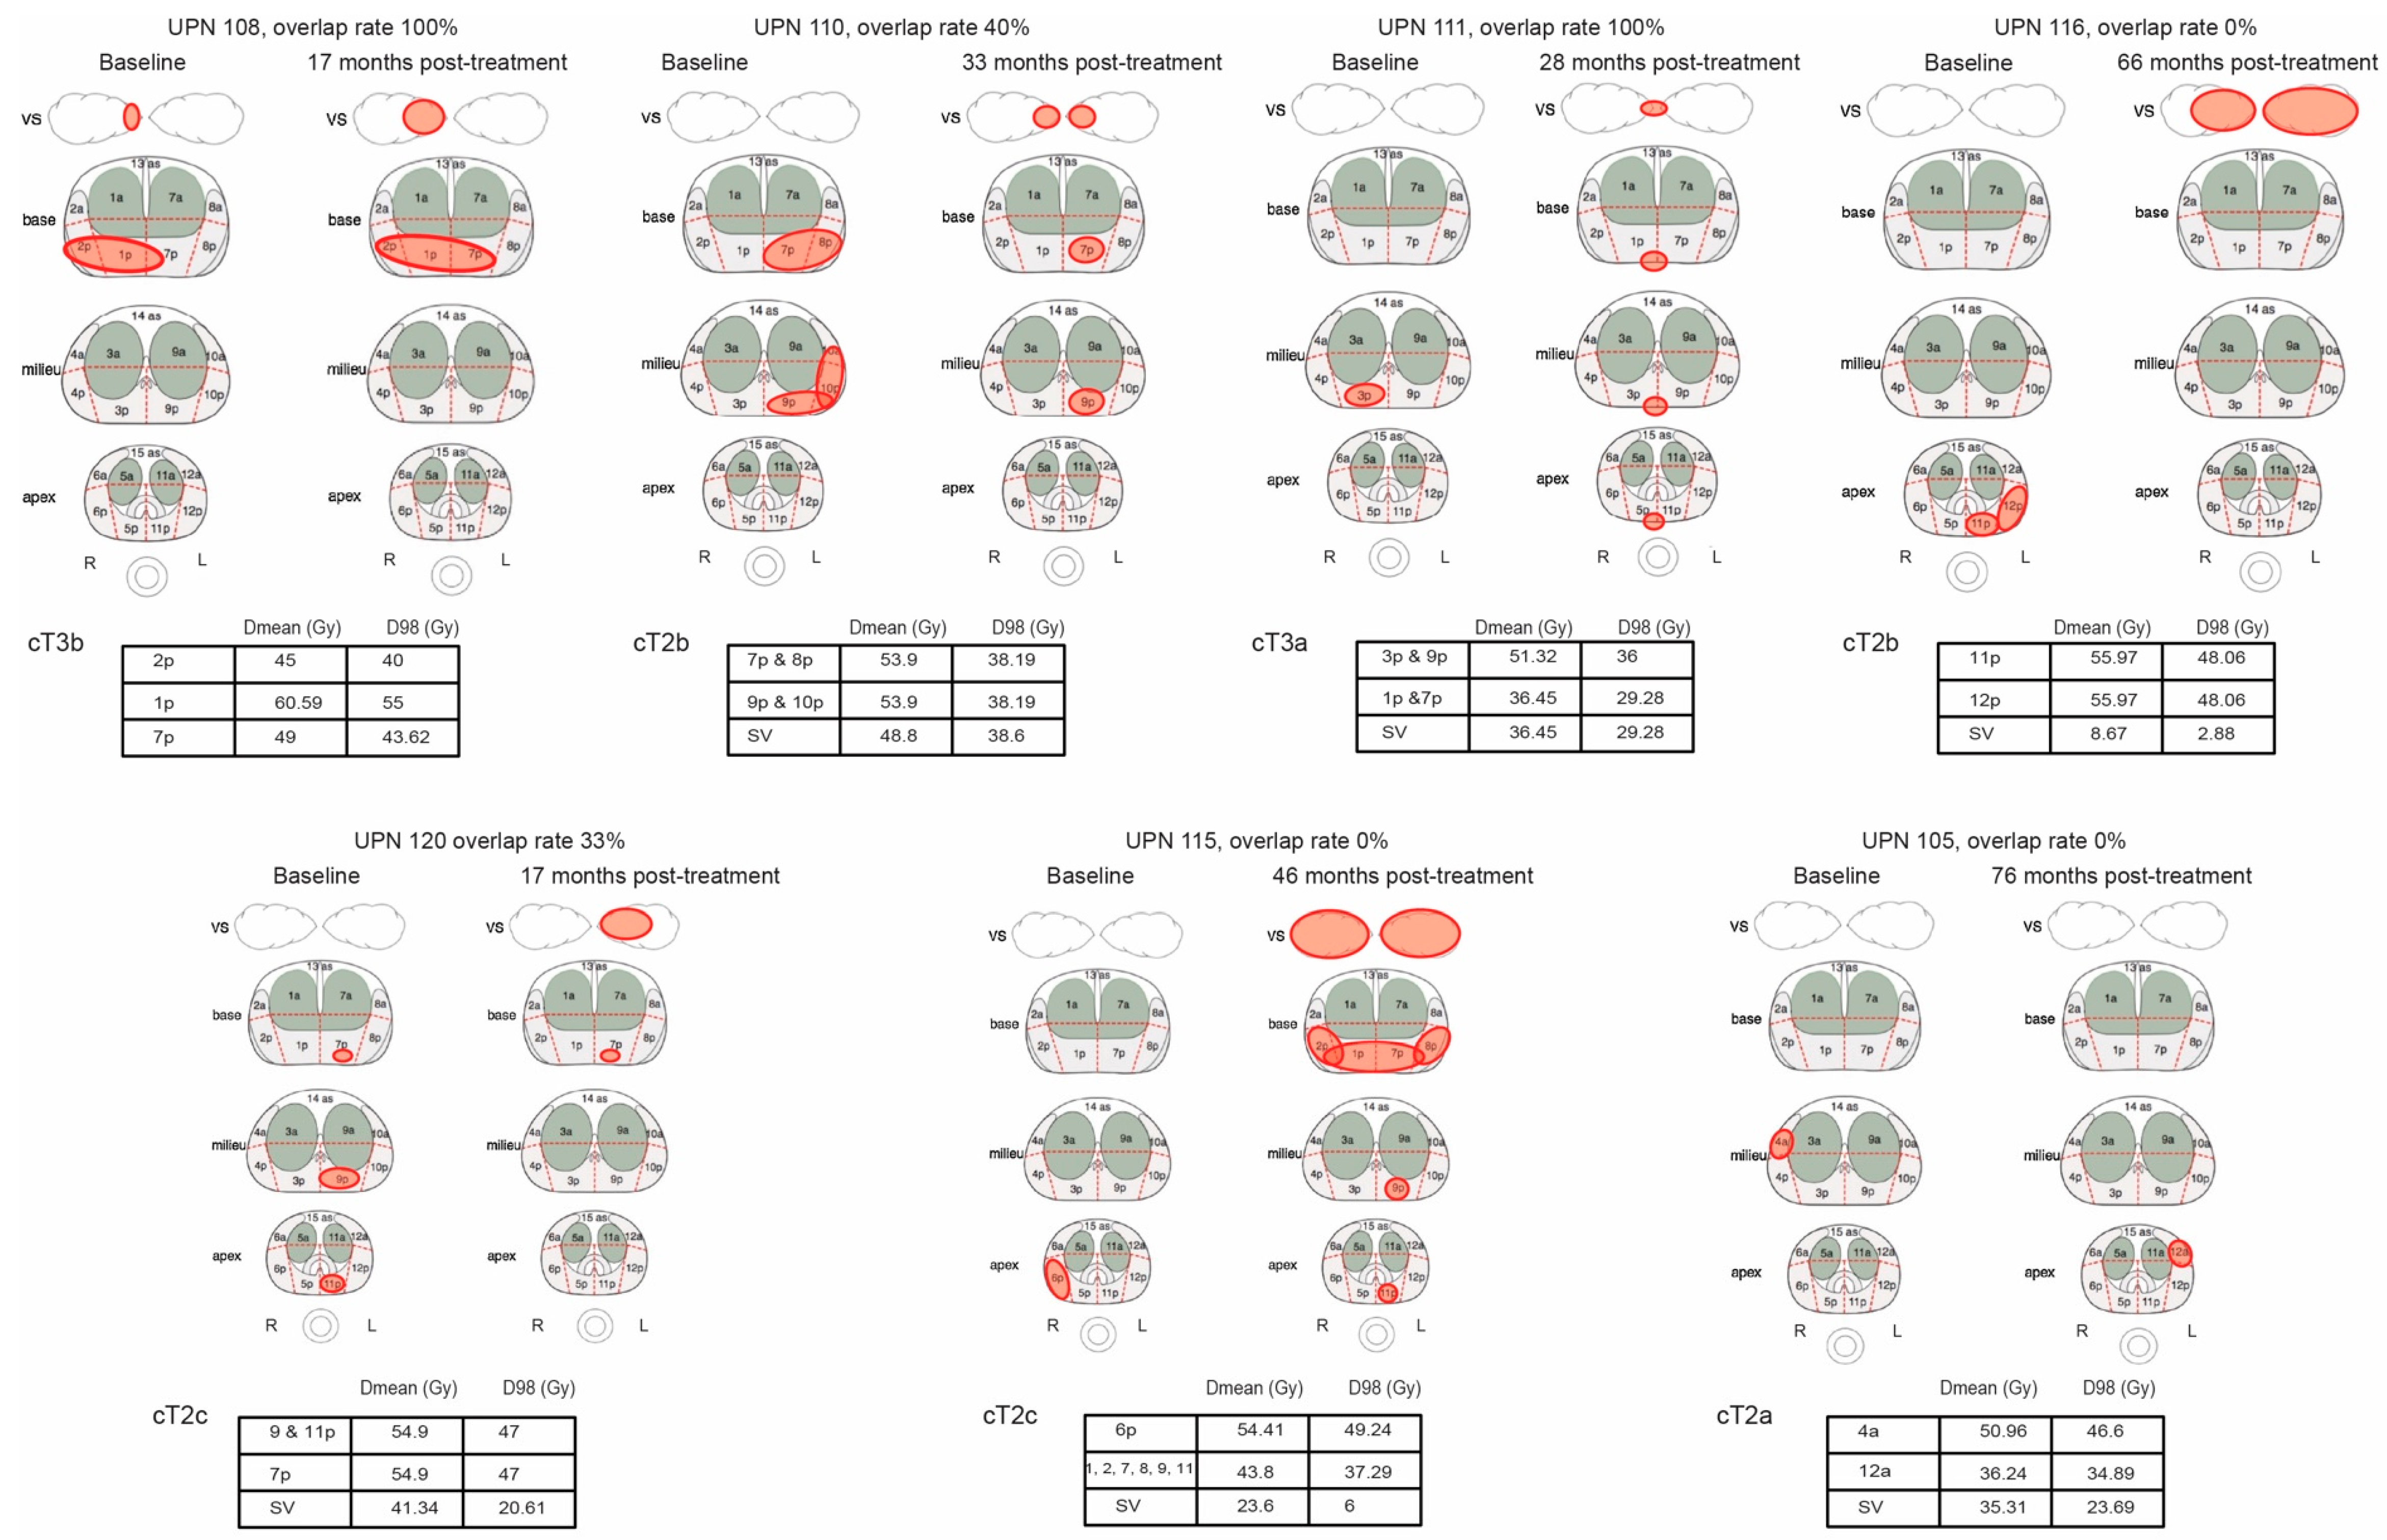

3.1. Pattern of Recurrence